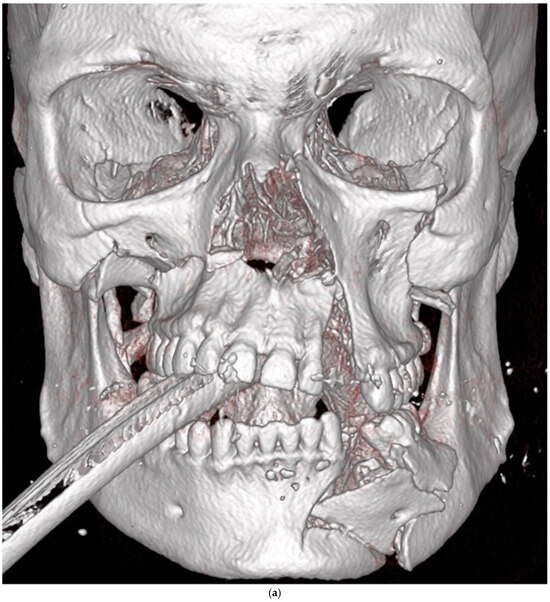

| Zygomatico–orbital complex * | 6 | 4 | 6 inadequate reductions | ||

| Le Fort ** | 4 | 1 (Le Fort III) | 4 inadequate reductions | ||

| Orbit | 4 | 0 | 3 inadequate reconstructions of orbital floor fractures, 1 orbital deformity due to inadequate reduction of the zygomatic bone | ||